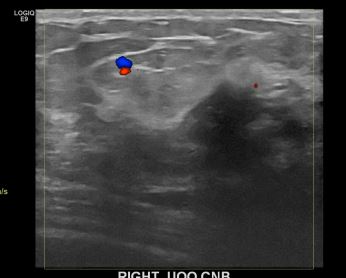

상기환자는 외부검진이상소견으로 조직검사위해 내원하신 40대후반

여성분으로 의심스러운 우측혹 조직검사 시행해 침윤성암 으로 진단되었습니다